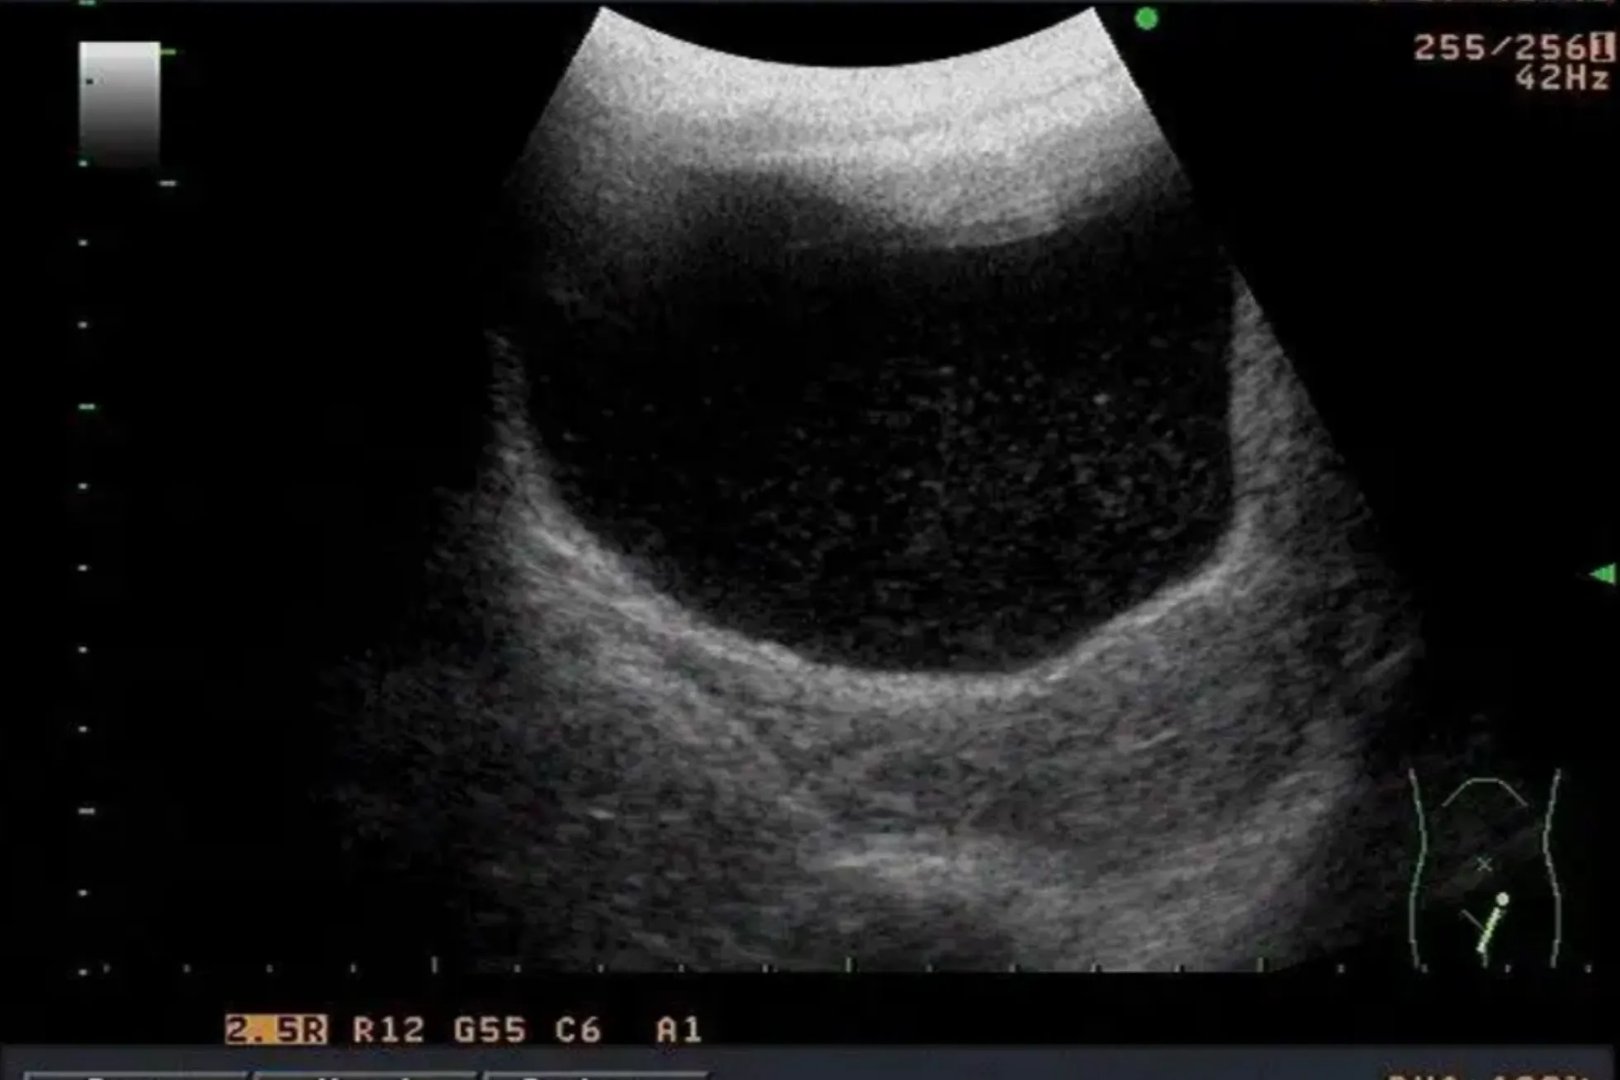

的有关信息介绍如下:彩超是彩色多普勒超声的简称,可对血管、腹腔脏器、心脏、子宫及附件、小器官、前列腺及精囊等全身性脏器进行检查。